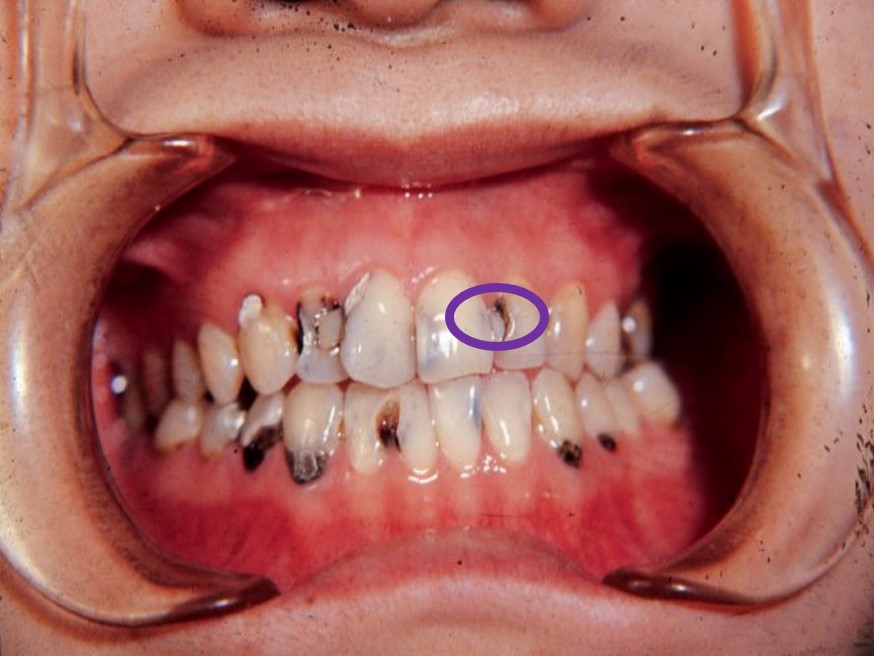

2)好发牙面及部位

★咬合面点隙窝沟(图7.1-3)>邻面接触点下方(图7.1-4)>唇颊面的近龈缘牙颈部及磨牙颊侧点隙 (图7.1-5)

图7.1-3 咬合面点隙窝沟

图7.1-4 邻面接触点下方

图7.1-5 唇颊面的近龈缘牙颈部及磨牙颊侧点隙